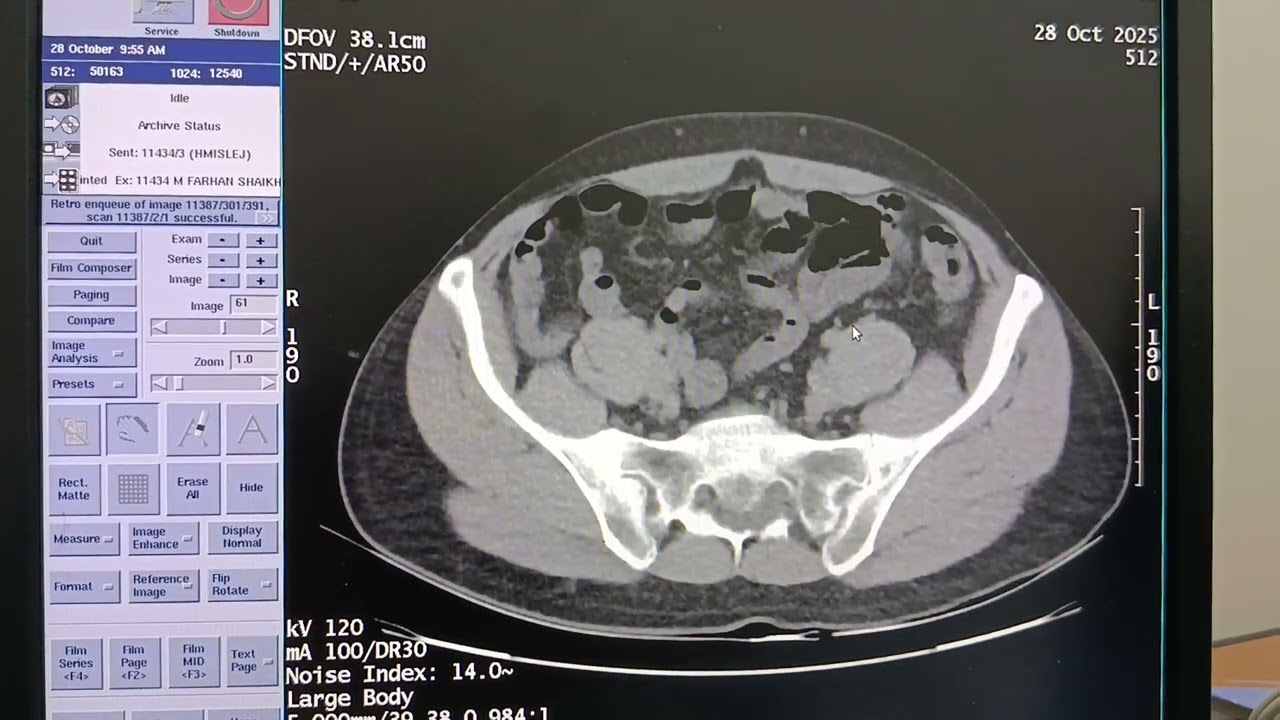

CT KUB (Kidneys, Ureters, and Bladder) — including preparation, indications, and diagnostic interpretation.

CT KUB is a non-contrast computed tomography scan of the kidneys, ureters, and bladder.

It’s the gold standard imaging study for detecting urinary tract stones and other urinary abnormalities.

4. Diagnostic Findings & Interpretation

1. Urinary Calculi (Stones)

Hyperdense (bright) focuses on CT, usually without contrast.

Can identify:

Size, location, and number of stones.

Hydronephrosis (dilated collecting system upstream).

Perinephric fat stranding → sign of inflammation.

➤ 2. Hydronephrosis

Dilated renal pelvis and calyces.

May be secondary to obstruction by a stone, mass, or stricture.

➤ 3. Masses / Tumors

Non-contrast CT can show space-occupying lesions in the kidney